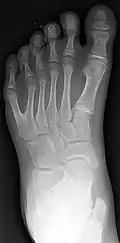

Diagnosis

Classification is performed by using x-ray imaging to see the bone structures.[17] In 1961, Frantz and O'Rahilly proposed that congenital anomalies of the limb could be classified in seven categories, based on the embryonic failure causing the clinical presentation. These categories are failure of formation of parts, failure of differentiation, duplication, overgrowth, undergrowth, congenital constriction band syndrome, and generalized skeletal abnormalities.[36] In 1976 this was modified by Swanson.[37] Polydactyly belongs to the category of duplication.[12] As of 2009, research has shown that the majority of congenital anomalies occur during the 4-week embryologic period of rapid limb development.[12]